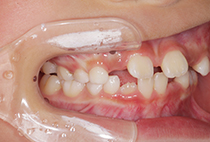

20代女性の患者さま。

八重歯の見た目が気になってご来院されましたが、実は顎の痛みや開口障害など、顎関節症の症状もありました。

そのため、かみ合わせと顎関節症の治療を同時に行ったにもかかわらず、2年間で治療が終了。

かみ合わせが整い咬筋の過緊張も改善しました。咬筋の肥大も治ってフェイスラインがすっきりしました。

最終的には美しい歯並びと、安定した痛みのないかみ合わせが実現しました。

八重歯が気になる

叢生、顎関節症、開口障害

20代女性

矯正治療2年

24回

唇側矯正

矯正:1,161,600円+毎月調整量:6,050円

しっかり前歯を下げるために、インプラントアンカーを使用してコントロールしました。

かみ合わせが整うと咬筋の過緊張が改善。

過緊張による筋肉肥大も改善しフェイスラインもすっきりしました。